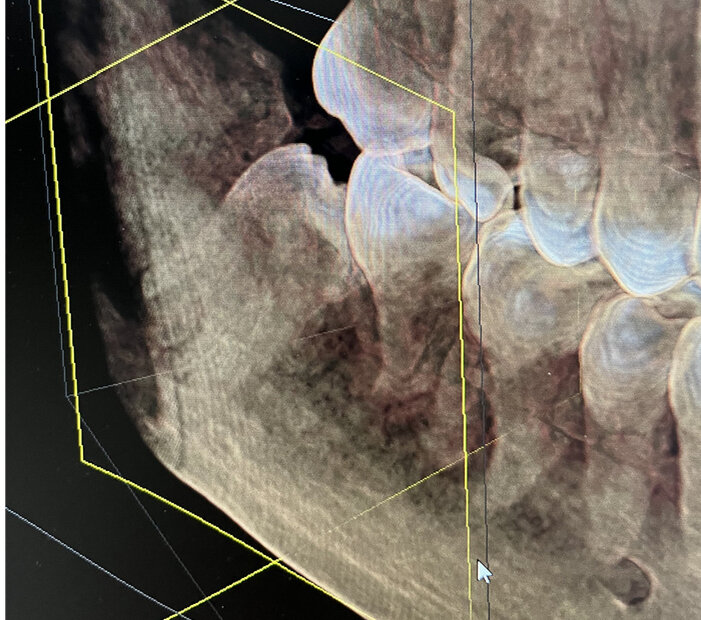

Договорившись с главврачом, который тоже удаляет такие зубы, я отправился на компьютерную томографию. Когда я увидел зуб на снимке, я схожу понял, что операция будет непростой.

-2

Восьмерка лежала горизонтально, причем перпендикулярно телу нижней челюсти, причем прямо на нижнем альвеолярном нерве, вдобавок имела сросшиеся корни с утолщением на конце, смотрела в корень языка и полностью покрыта плотной кортикальной костью.

Фото зеркальное. Всё дело происходит справа.